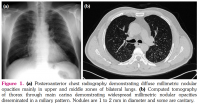

At the end of four years, chest radiography demonstrated diffuse millimetric nodular opacities mainly in upper and middle zones of bilateral lungs (Figure 1a). Computed tomography (CT) of thorax revealed widespread millimetric nodular opacities disseminated in a miliary pattern on bilateral lungs in the absence of hilar or mediastinal lymphadenopathy. The nodules were 1 to 2 mm in diameter and some of them were cavitary (Figure 1b). The patient was free of any symptom and routine laboratory analysis was normal. Pulmonary function tests were within normal limits. A written informed consent was obtained from the patient.